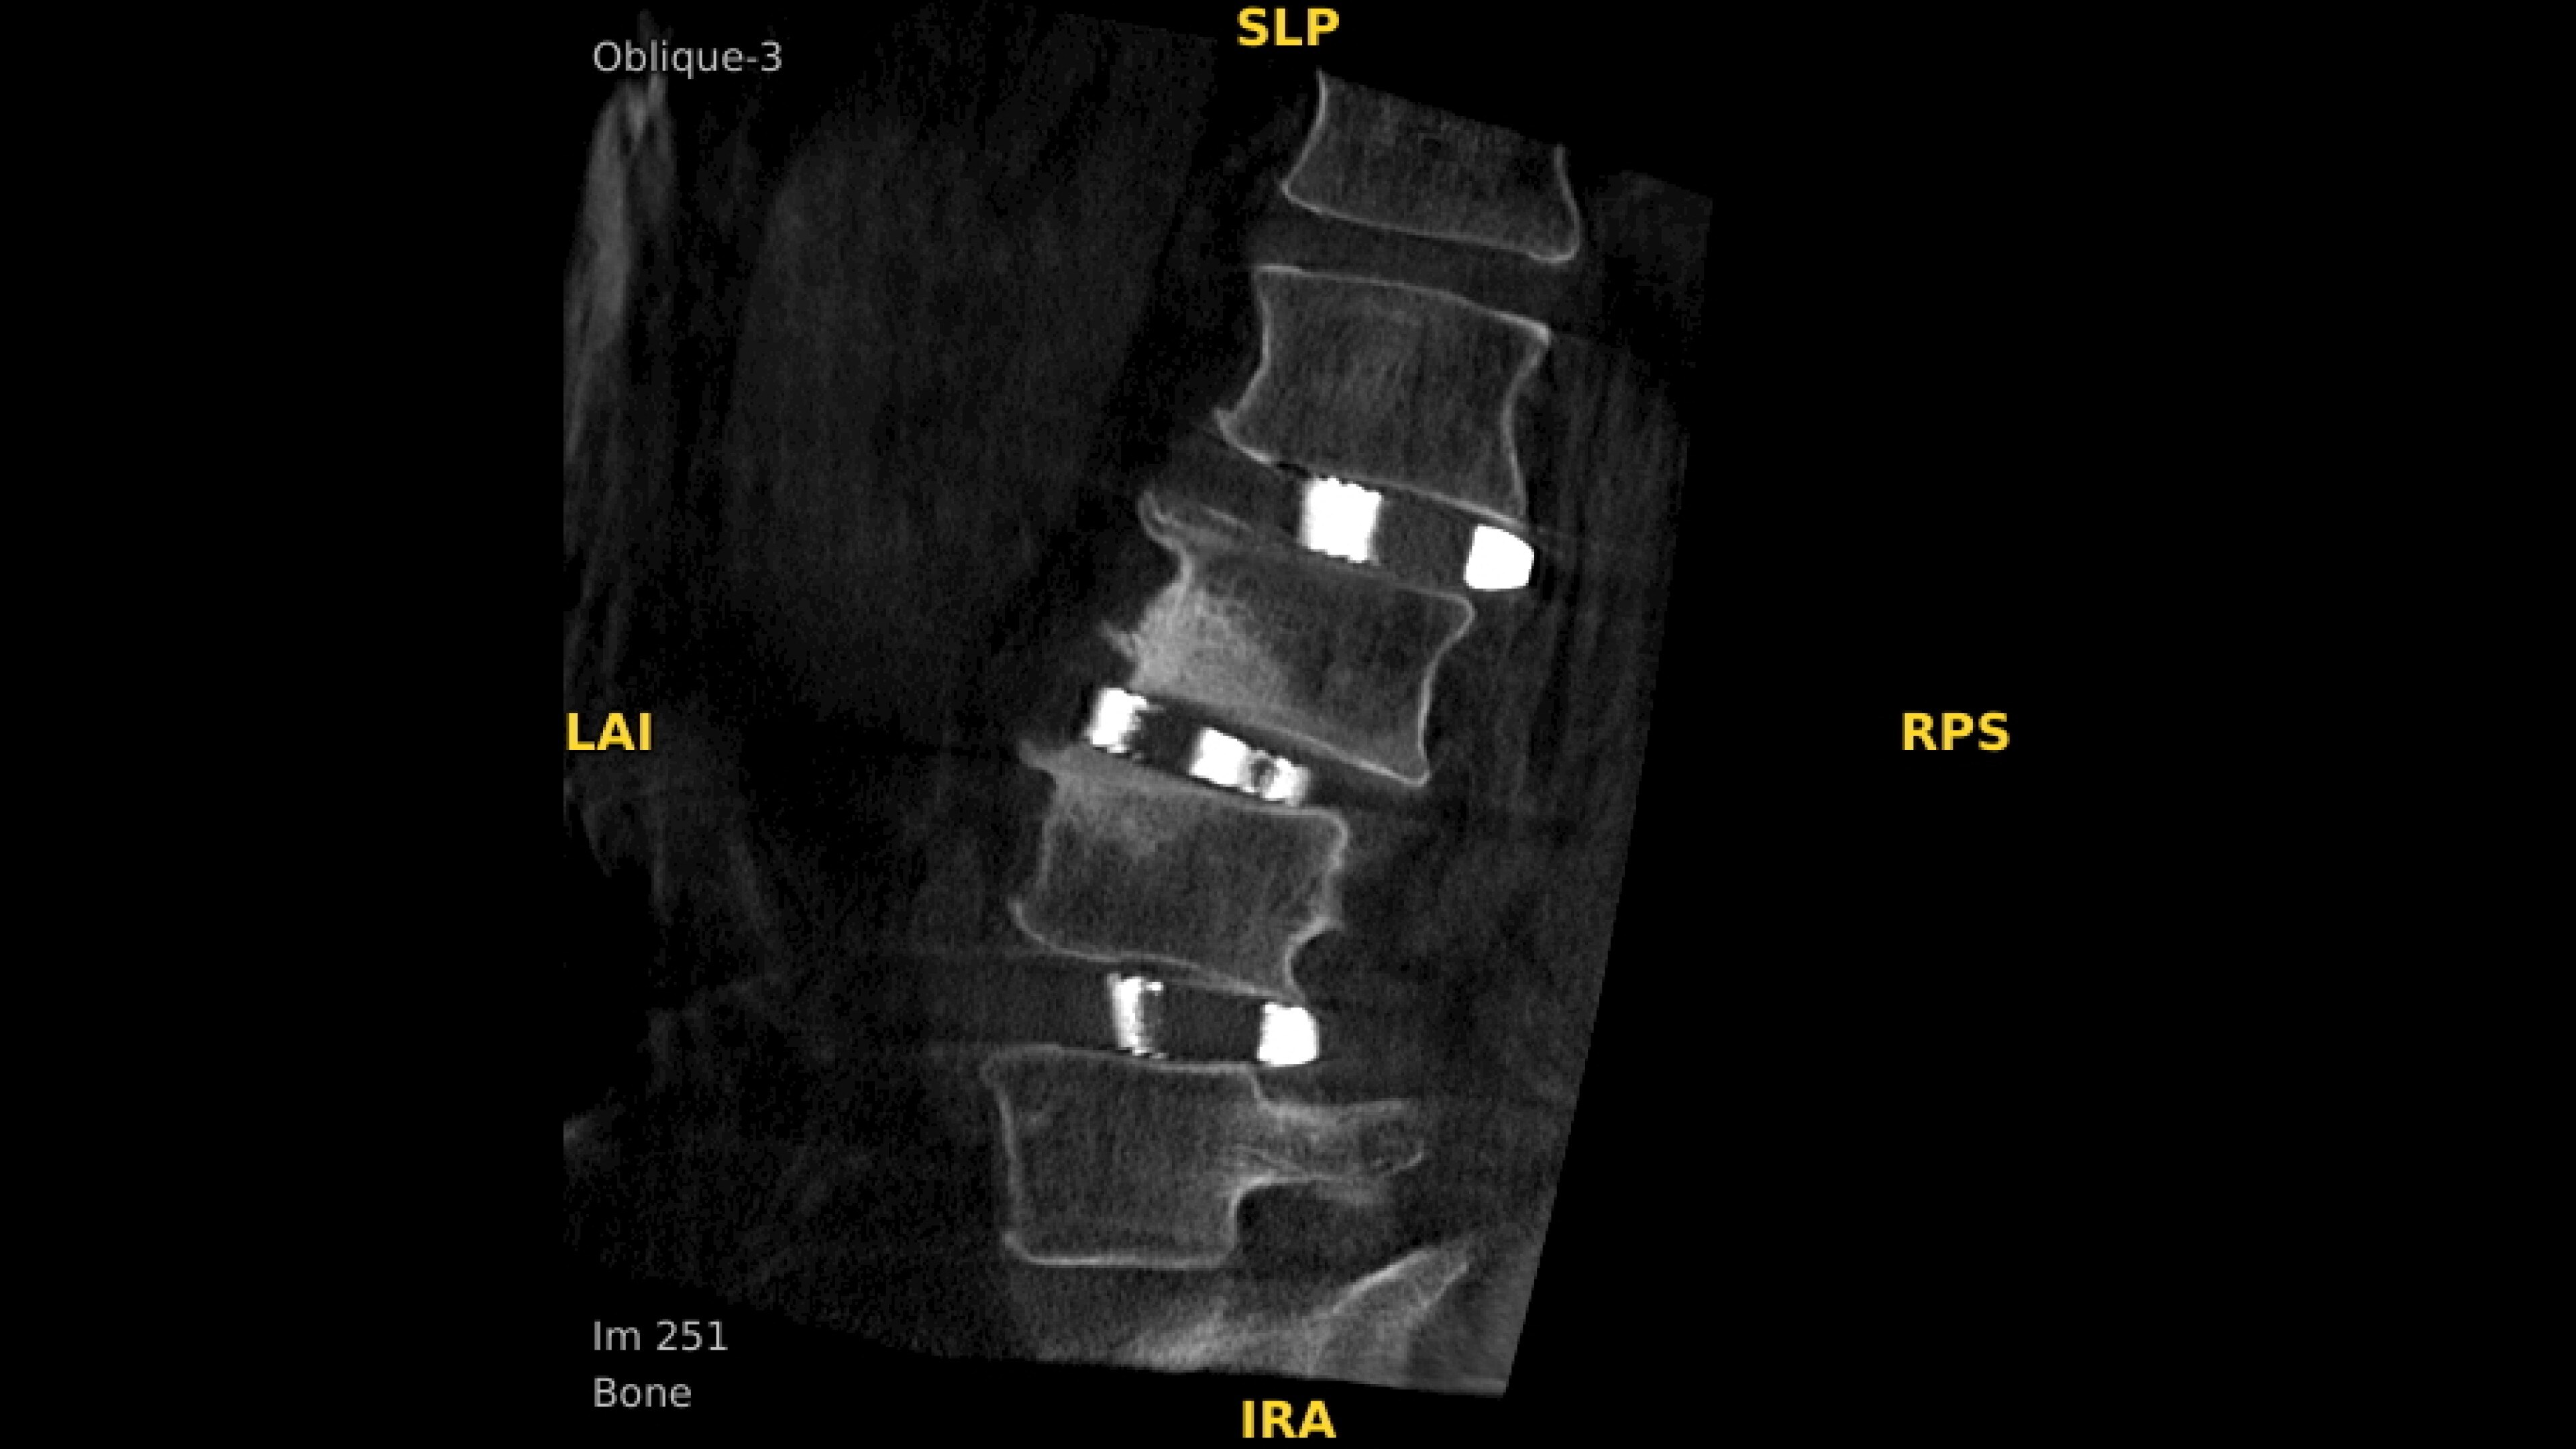

Enhance intraoperative decision-making with visualization capabilities of Augmented Fluoroscopy in the OEC 3D Volume Viewer. Analyze five perspectives with 3D imaging tools including Multi-Oblique Mode, scrolling 512 slices, zoom, and more.